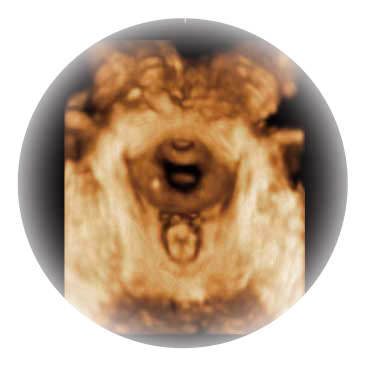

可同时显示组织结构表面和内部的轮廓信息,达到透视效果,为临床提供更丰富的诊断信息。

大角度腔内容积探头,可完整包络子宫及盆底结构,充分展示组织结构毗邻关系。